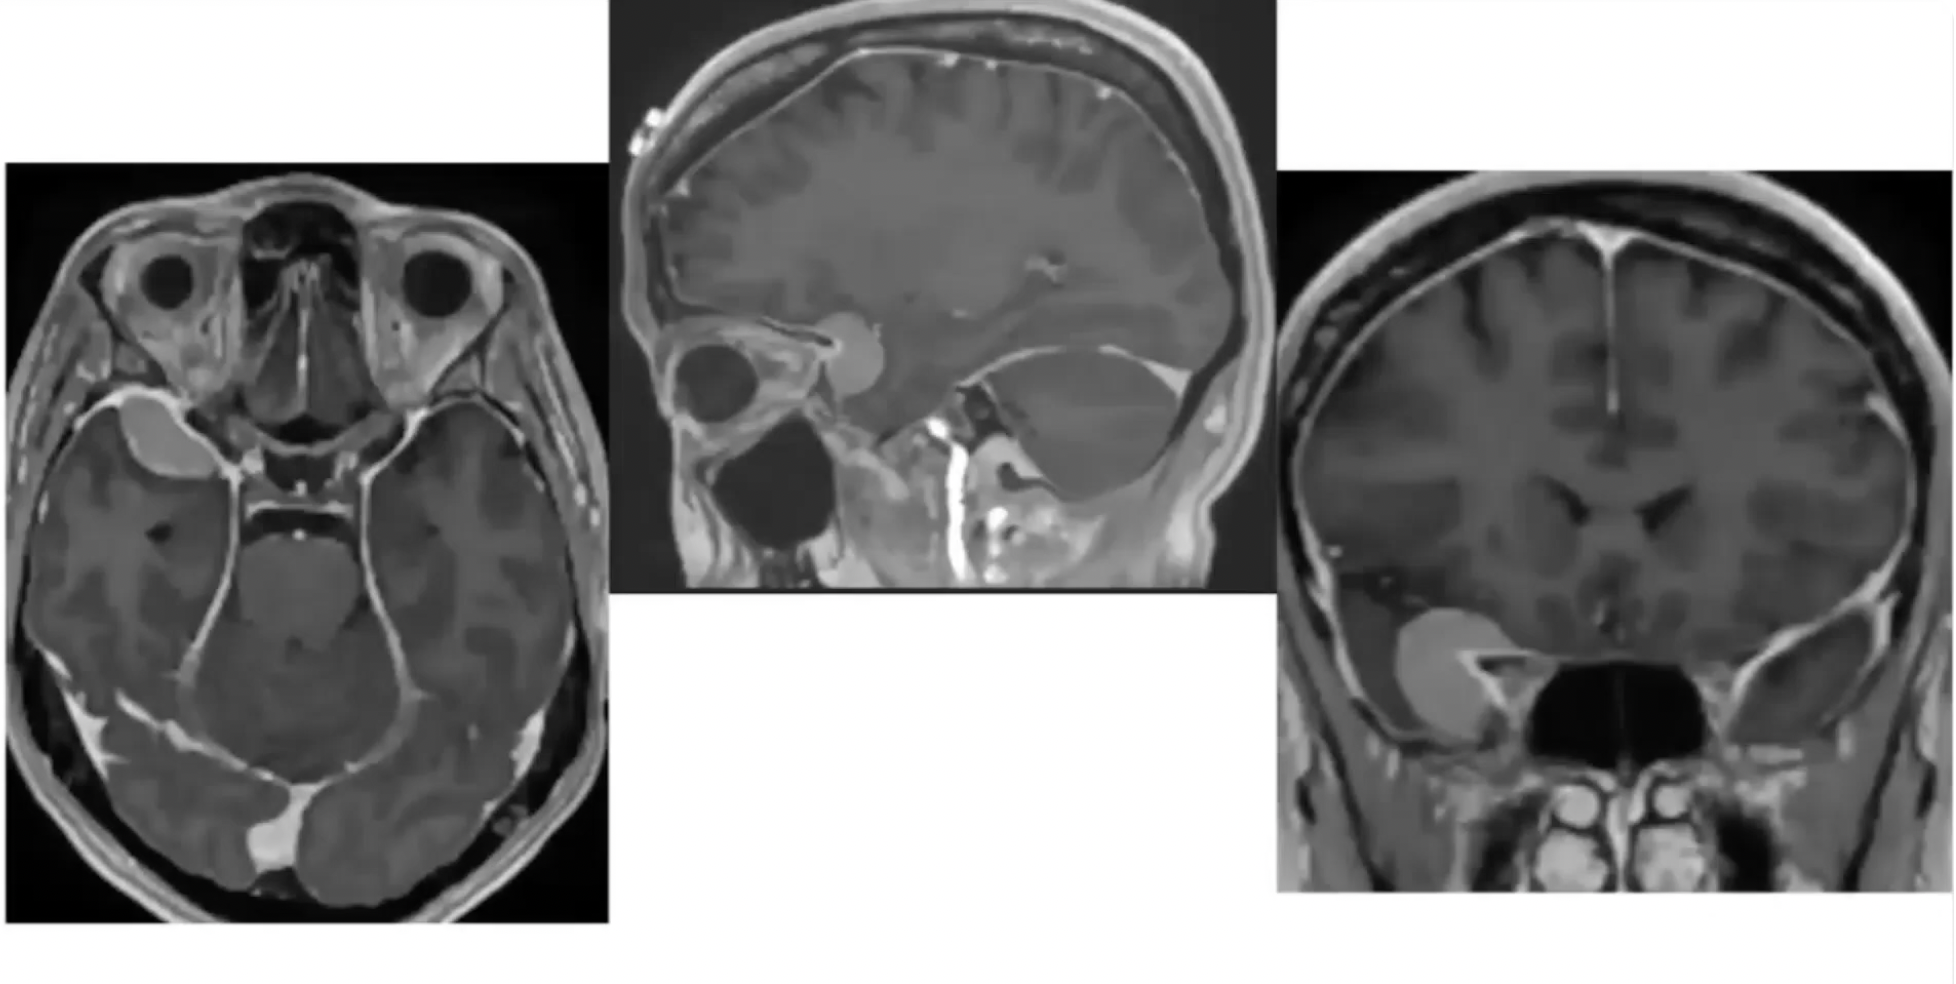

A way to improve skull base surgery through the advanced application of endoscopic techniques.